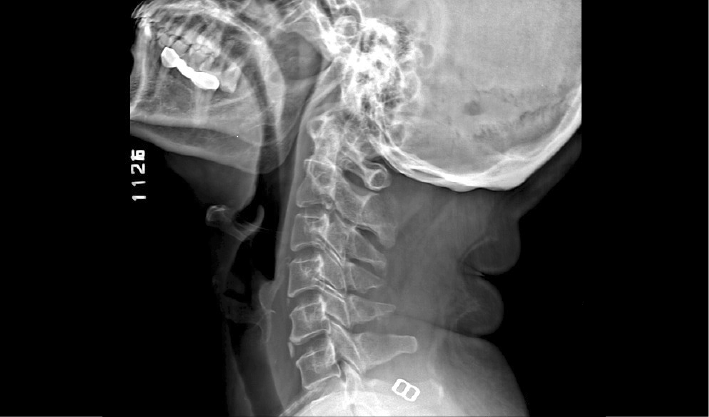

高清成像助力精准诊断

成熟优秀的动态成像技术,在透视下实时观察内部器官运动状态,并可快速高清点片,动静结合,多视角精准观察病灶。